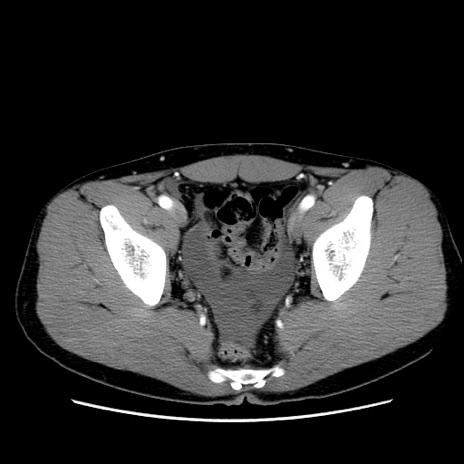

症例36(横断像)

【症例】20歳代 男性

【主訴】心窩部痛

【現病歴】今朝より上腹部痛あり。一旦軽快していたが再度出現したため救急要請。昨日夕に白身の魚を含む刺身を食べた。

【身体所見】BP 136/89mmHg、HR 74/min、BT 37.0℃、腹部:膨満、軟、心窩部に圧痛あり。反跳痛なし、筋性防御なし、腸雑音やや亢進あり。

【データ】WBC 17700、CRP 0.48